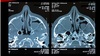

2

3